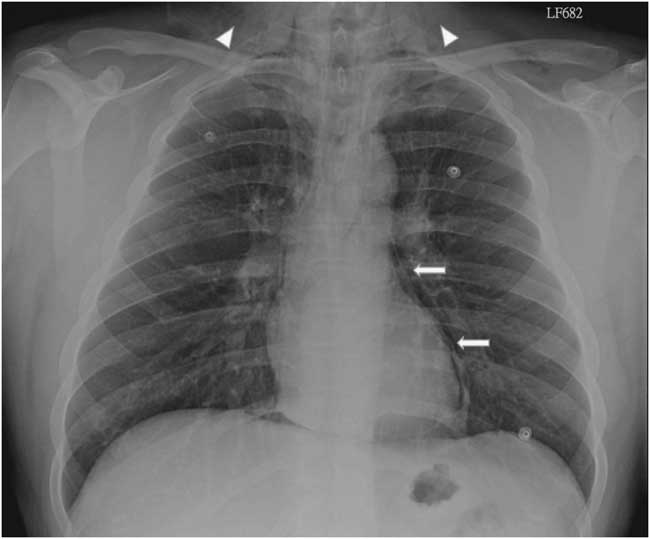

A 22-year-old male presented to the emergency department due to progressive odynophagia and dysphagia. He underwent a left third mandibular molar extraction at the dental clinic a week prior. At the emergency department, vital signs were normal except tachycardia (114/min) and tachypnea (22/min). A physical examination revealed bilateral neck tenderness with crepitus on palpation, no stridor or acute airway compromise signs. Laboratory data showed leukocytosis (white blood cell count, 19000/cumm; segmented, 91%) and elevated C-reactive protein (1.07 mg/dL). Radiographs showed the presence of prevertebral emphysema on the C-spine lateral view (Figure 1) and subcutaneous emphysema with pneumomediastinum on the chest posteroanterior view (Figure 2). A non-contrast computed tomography (CT) scan confirmed the radiographic findings; additionally, there was gas collection over the pericarotid, pericardial (Figure 3) and extradural spaces (Figure 4). Because there was no CT evidence of infectious signs and clinical features were stable, conservative treatment with intravenous amoxicillin/clavulanic acid was given for a week. Clinical symptoms improved, and a follow-up CT showed no residual gas.

Figure 1 C-spine radiographs (left lateral view) show prominent subcutaneous and prevertebral emphysema from the base of the skull to the mediastinum.